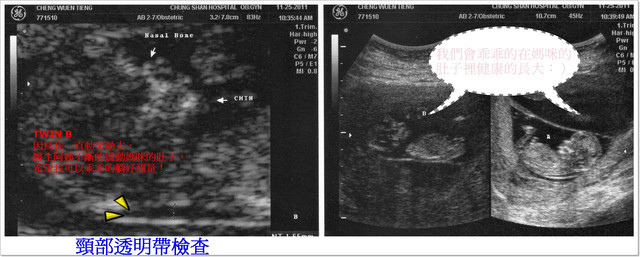

B寶寶身長:5.97公分(比一般值還大) 心跳:160/分

【頸部透明帶】檢查可以提早發現染色體異常及唐氏症,

所謂【頸部透明帶】(Nuchal translucency NT)

是指在第一孕期利用超音波觀察於胎兒頸部後的皮下積水的空隙,

在超音波掃描時會呈現透明帶狀,再測量介於皮膚和組織之間的最大空隙厚度。

如果厚度超過2.5mm或是3mm,就代表胎兒屬於唐氏症的高危險群,

也就是胎兒後頸部透明帶越厚,罹患有先天性疾病的機率越高,

此時,醫師會建議進一步用絨毛膜採樣或是羊膜穿刺檢查胎兒染色體。

只有B寶寶比較頑皮,一直貼著羊膜,醫生不斷的又揉又震動我的肚子,

希望寶寶可以乖乖的躺好,果然寶寶在躺下來的時候後頸部出現一條黑色的帶子,

就是要測量這條帶子的厚度,要是太厚(超過3mm)就表示有唐氏症的危險哦!

呼~還好!最後測量的數值在標準範圍之內!

今天檢驗出來結果,每一項都是正常的,真是太好了((開心ing))

寶貝們,要乖乖的在媽咪的肚子裡健康的長大喲:)